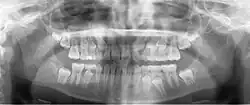

A basic panoramic radiograph